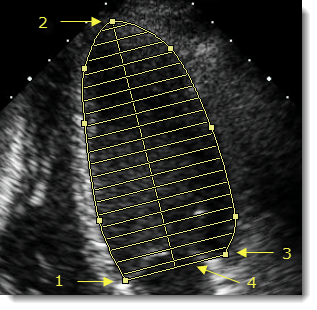

- Κάντε κλικ στο ένα άκρο (1) της βάσης της κοιλότητας για να τοποθετήσετε την πρώτη λαβή του εργαλείου σήμανσης.

- Κάντε κλικ στο περίγραμμα της κοιλότητας στην κατεύθυνση της κορυφής (2) για να τοποθετήσετε επιπλέον λαβές για ακριβή σχεδίαση περιγράμματος της περιοχής του.

- Αφού τοποθετήσετε αρκετές λαβές κατά μήκος του περιγράμματος της κοιλότητας, κάντε διπλό κλικ στο άλλο άκρο της βάσης (3) για να ορίσετε την πρώτη λαβή.

Η γραμμή βάσης (4) ολοκληρώνεται αυτόματα και σχεδιάζεται ο μεγάλος άξονας έως την κορυφή της κοιλότητας. Ο όγκος της κοιλότητας υπολογίζεται με τη μέθοδο των δίσκων, βάσει των 20 δίσκων που οπτικοποιήθηκαν στην εικόνα.

- Για βελτίωση του υπολογισμού, επιλέξτε τη σήμανση και κάντε κλικ στις λαβές του περιγράμματος για να προσαρμόσετε το σχήμα ή σύρετε τη λαβή του μεγάλου άξονα (2) για να μετατοπίσετε την ευθυγράμμιση των δίσκων.